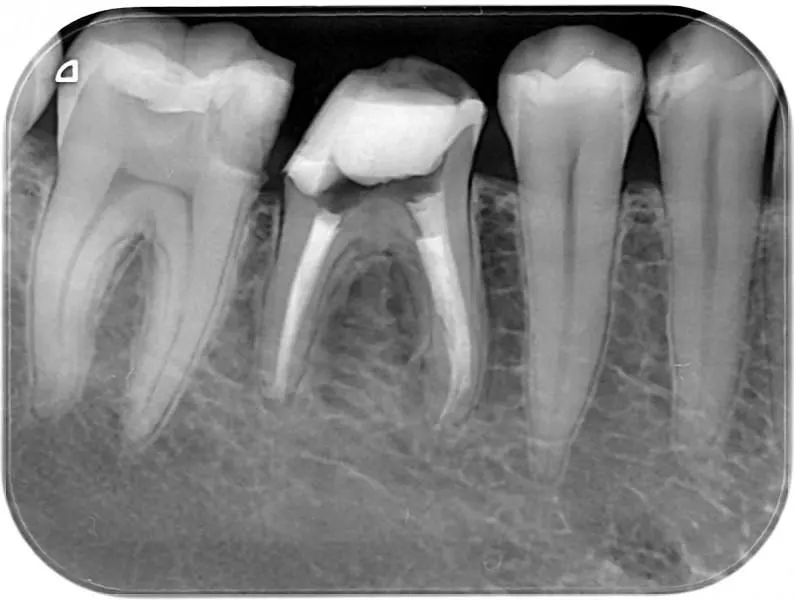

Снимка

след